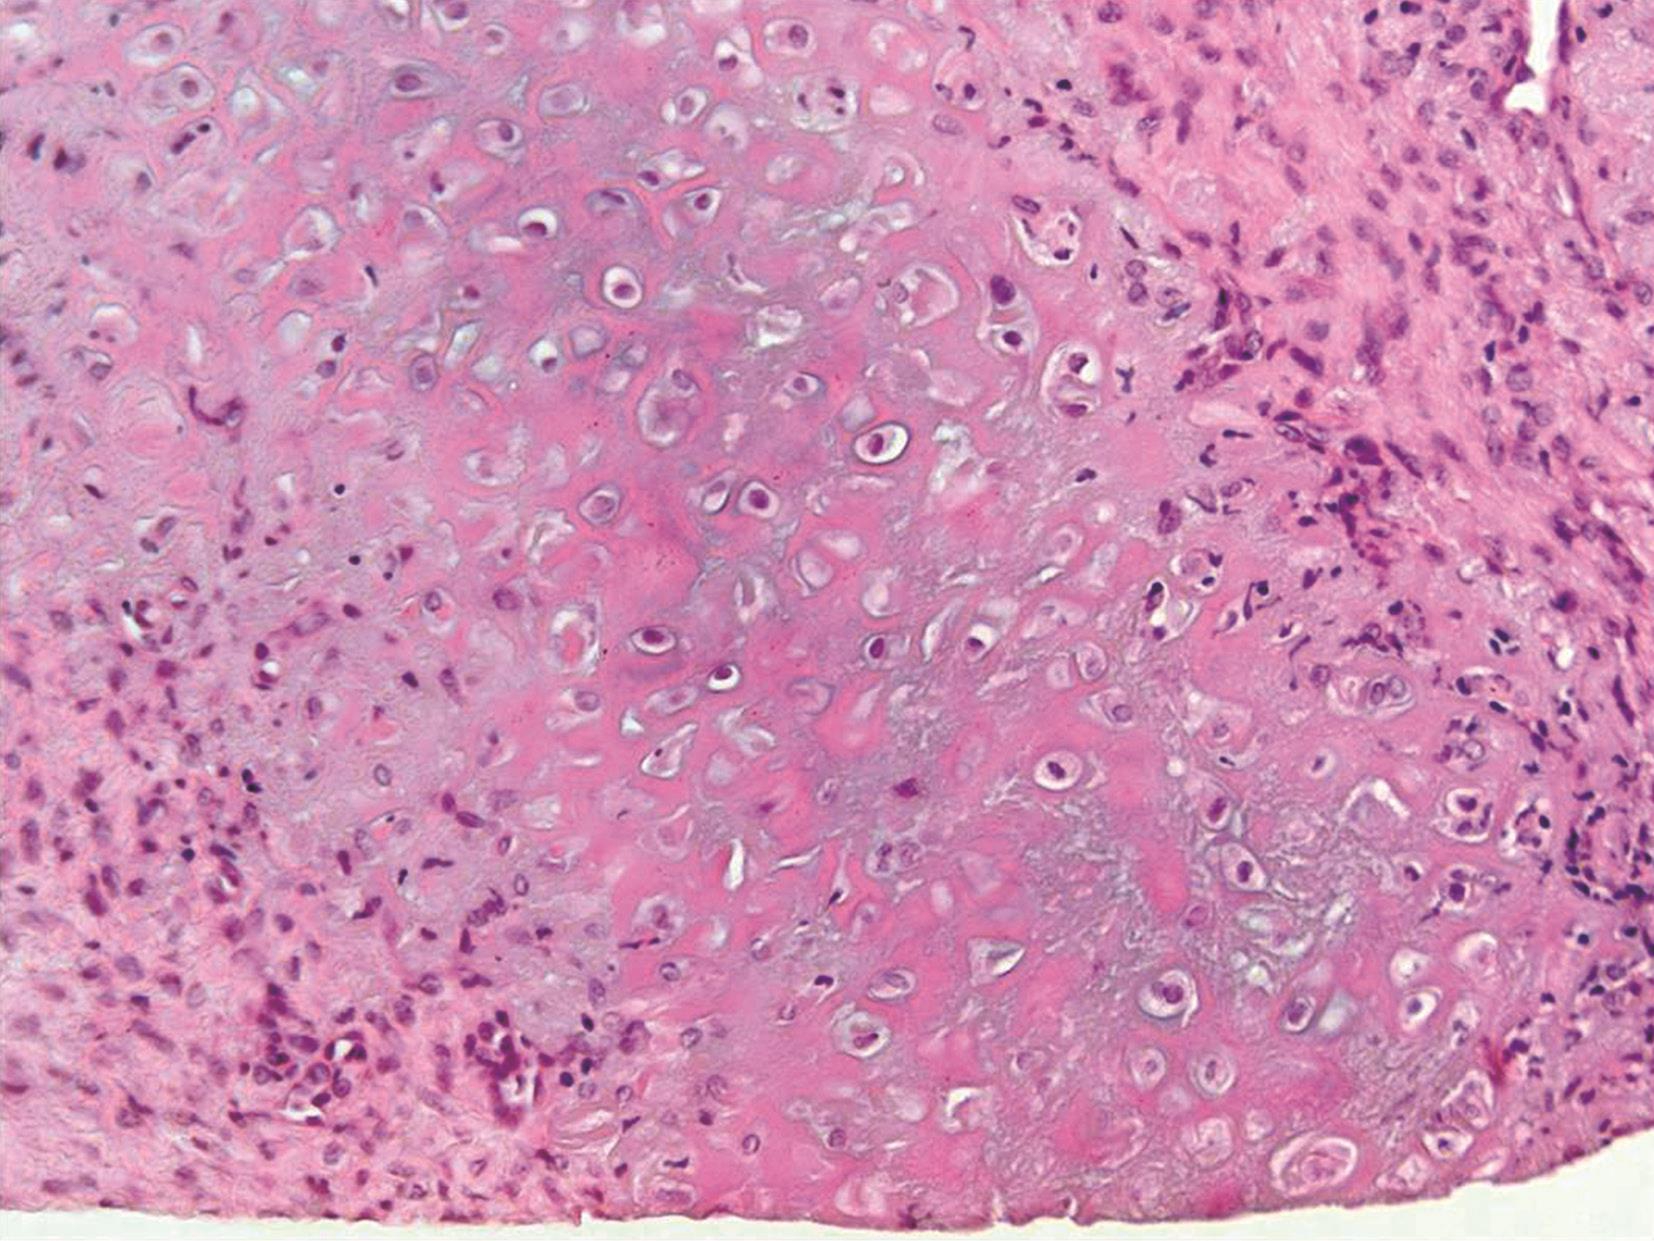

文献总结RP的病理改变表现为:早期软骨基质的嗜碱性丧失,伴随局灶性软骨细胞固缩、软骨陷窝崩解,并可见嗜酸性基质纤维化改变。上述变化在软骨膜处更为明显。镜下亦可见软骨板的边缘性侵蚀,软骨陷窝间隙变窄及软骨细胞受压变形。胶原纤维呈不规则螺旋样排列,散布在浆细胞及淋巴细胞周围(图3-1)。此时尚未出现软骨基质的异染性改变。病变进一步发展可见肉芽组织形成及明显的局部钙化及骨化。硫酸软骨素可抑制钙与受损主动脉结合,而酸性黏多糖的缺失将导致过度钙化。类似的情况也适用于软骨溶解过程。RP最初的病理改变为软骨基质酸性黏多糖缺乏的假说,该假说得到了针对正常及病理软骨对比研究的支持。1984年Homma等还在RP患者血清内检测到了抗Ⅱ型胶原抗体,证实病变软骨内有免疫球蛋白、纤维蛋白原及补体C3的颗粒样沉积。然后,软骨细胞出现浓缩,最终凋亡,软骨基质被严重破坏并被纤维结缔组织替代,还可有胶凝状囊肿和钙化区。

图3-1 软骨炎的病理改变